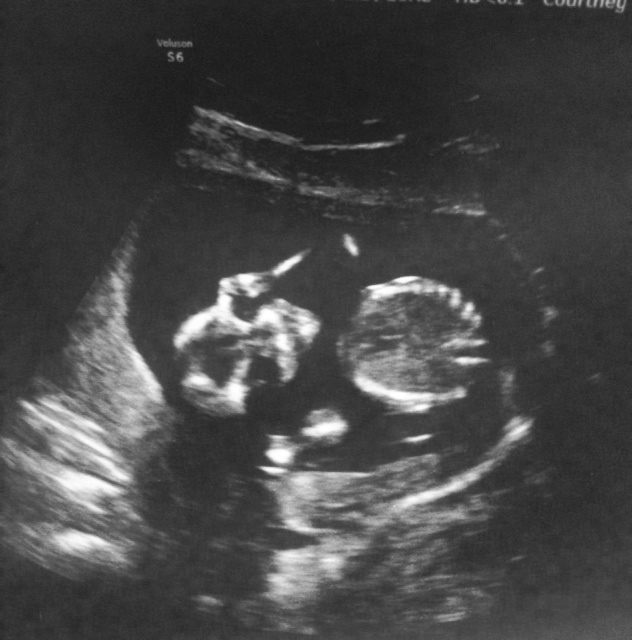

First of all sorry if the images aren't too clear they are pictures of a picture!!

So we get to see our little one and within a few minutes the tech asks us if we want to know what we are having. YES!!!! I reminded her I was only 15 weeks but she said BOY!!! She checked several times and even made sure she wasn't seeing the umbilical cord and said there was no doubt in her mind we are having a boy!! We didn't get the best profile pic of him cause he was sleepy and wasn't moving much. We did get to see him yawn and stretch his little fingers out and I melted and fell even harder in love with him!!!